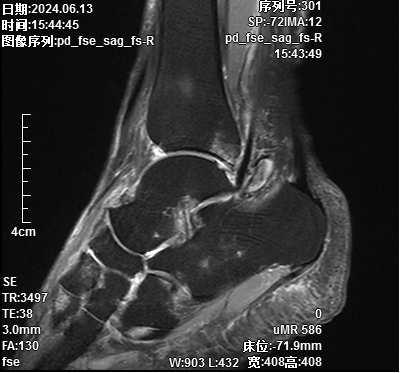

术前标记体位

术中精细操作,切除病灶